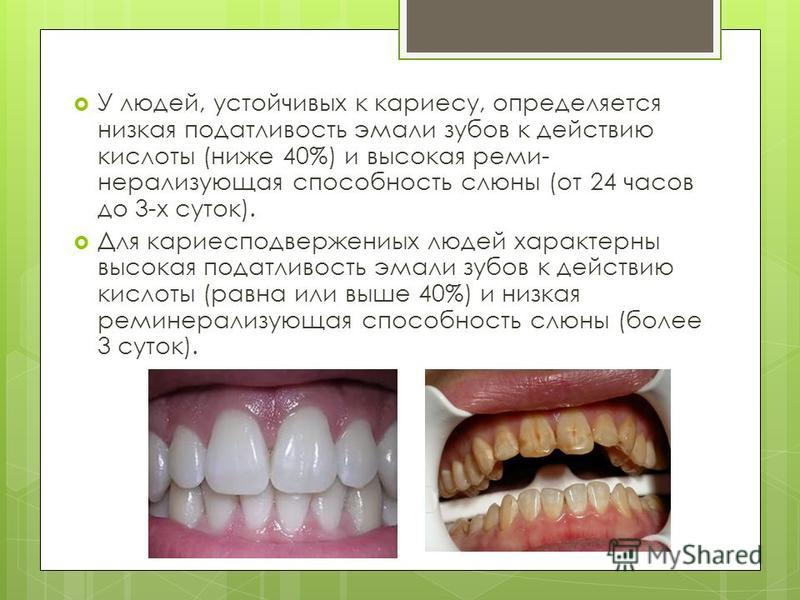

Как безопасно избавиться от пятен на зубах: проверенные методы

В этом разделе вы найдете полезные советы и рекомендации по удалению пятен с зубов, которые помогут вам вернуть улыбке белизну и здоровый вид. Мы расскажем о самых эффективных и безопасных способах борьбы с пятнами на зубах.